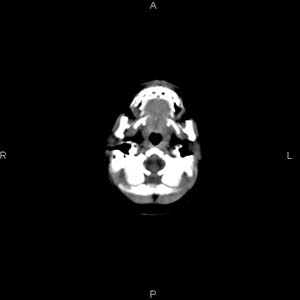

患者男,27天,出生后正常,今天中午在母亲怀里抱着吃奶在放下睡觉时发现后枕部慢慢出现一包块,来查头颅ct。无外伤史。包块内ct值47-51hu。请大家讨论。

皮下血肿,颅骨无缺如 ,颅缝无增宽。皮下血管破裂所因起。

头皮下血肿,局部枕骨略有凹陷

支持脑膜脑膨出,双侧侧脑室三角区周围脑白质对称性低密度影,考虑缺血缺氧性脑病或肾上腺性脑白质营养不良。

\"中午在母亲怀里抱着吃奶在放下睡觉时发现后枕部慢慢出现一包块,包块内ct值47-51hu。

颅骨无缺损,骨缝无增宽.支持头皮血肿(血管破裂)